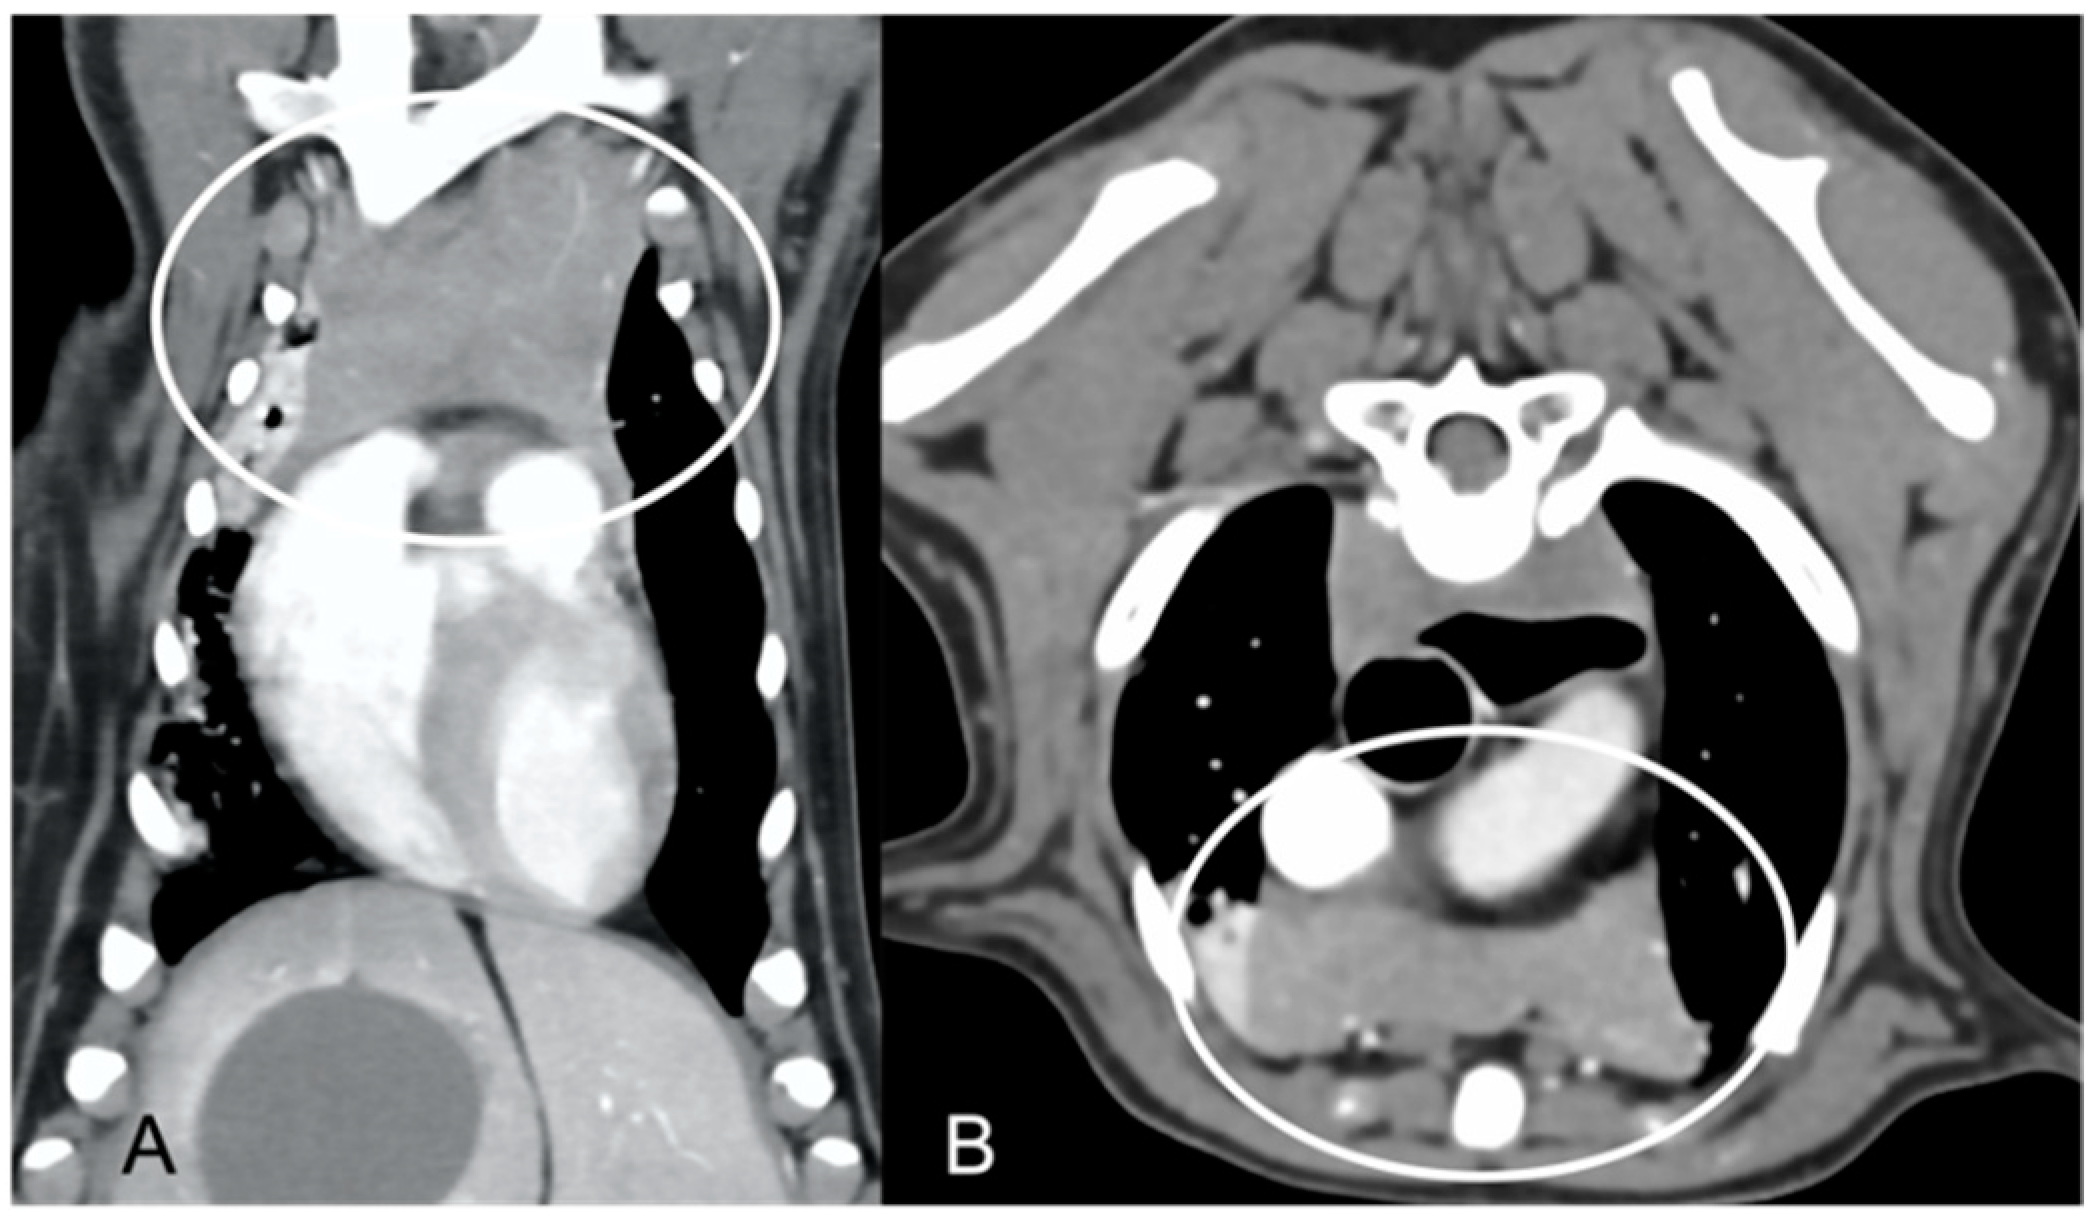

In both groups, most of the dogs presented with a triangular thymus (Figure 1); in the adult group, some dogs had an elongated thymus, and in the juvenile group, some dogs had a flattened thymus (Figure 2).

The overall appearance was lobulated in all of the adult dogs and homogeneous in all of the juvenile dogs (Figure 1 and Figure 3). The thymus was left-sided in all of the adult dogs, while it was located in the midline in a few juvenile dogs; one presented a thymus on the right side due to situs inversus (Figure 4). The maximum dimension of the thymus in the adult dogs group was always the length, while in some juvenile dogs, the maximum diameter was the width (Figure 2). The dimensions of the thymus were variable between different patients, with several breeds included and large differences in body weight between the dogs. For this reason, a ratio between the maximum diameter of the thymus (measured in cm) and the body weight (measured in kg) was calculated for each dog. The median ratio in the adult dogs group was 0.2 (minimum: 0.06; maximum: 0.4), while in juvenile dogs, it was 0.4 (minimum: 0.1; maximum: 1.4). The dogs with the higher ratio (>1) were in the juvenile group and they presented with spinal a cyst and enteritis and were 6 and 7 months old, respectively. The dogs with the lower ratio (<0.1) were in the adult group and they presented with muscular hemangiosarcoma (one dog) and synovial cell sarcoma (two dogs) and were 2, 6, and 8 years old, respectively.

Figure 1. Shape of the thymus (circled) in an adult dog (A) compared to a young dog (B). Post-contrast dorsal CT reconstruction. Note the different relative sizes of the thymus in the two dogs, and the heterogeneous (lobulated) appearance of the thymus in (A) with respect to the thymus in (B). In both cases, the shape of the thymus is triangular.